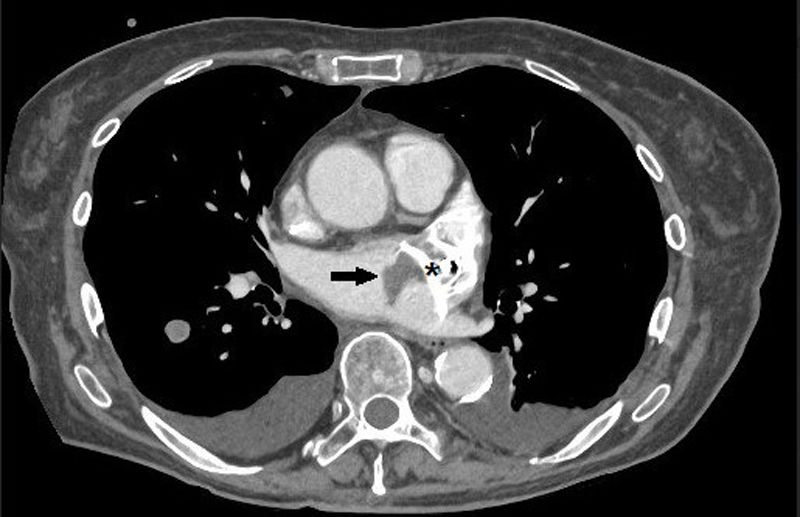

Late thrombosis of a left atrial appendage occlusion in a patient with cancer